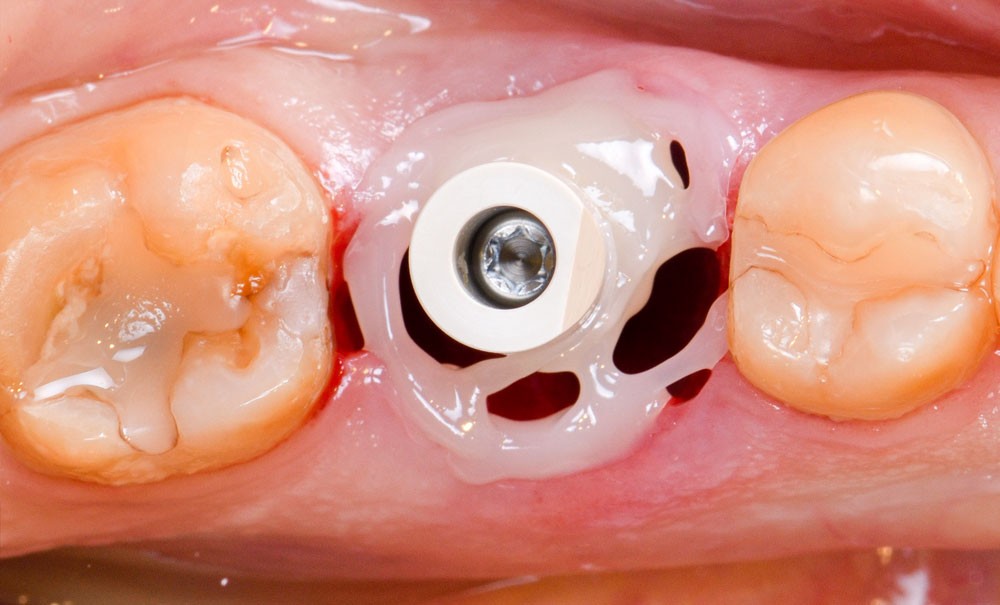

Prise en charge implantaire en secteur unitaire postérieur

Depuis quelques années, l’implantologie s’est largement répandue et démocratisée dans les cabinets d’omnipratique. Elle s’est imposée comme une discipline transverse, au carrefour de la chirurgie et de la prothèse. C’est probablement pour cette raison précise que le chirurgien omnipraticien est le mieux placé pour planifier, organiser et exécuter la réhabilitation implantaire dans son ensemble. Certes, certaines indications invasives (régénération osseuse avancée, par exemple) ou exigeantes (cas esthétique complexe) demeurent l’affaire des spécialistes. Il n’en reste pas moins que l’approche implantaire dans le secteur postérieur, qui représente la majorité des indications de remplacement de dent (échecs endodontiques, parodontaux ou prothétiques), est un acte routinier, de plus en plus traité par le chirurgien-dentiste.